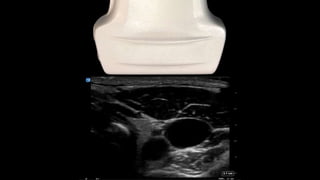

The document provides essential tips for vascular access using ultrasound, emphasizing the need for longer IV catheters to increase success rates. It suggests scanning for the largest and most superficial veins while being cautious of the free wall. Additionally, it highlights the importance of proper patient and machine positioning for optimal ergonomics and comfort during the procedure.